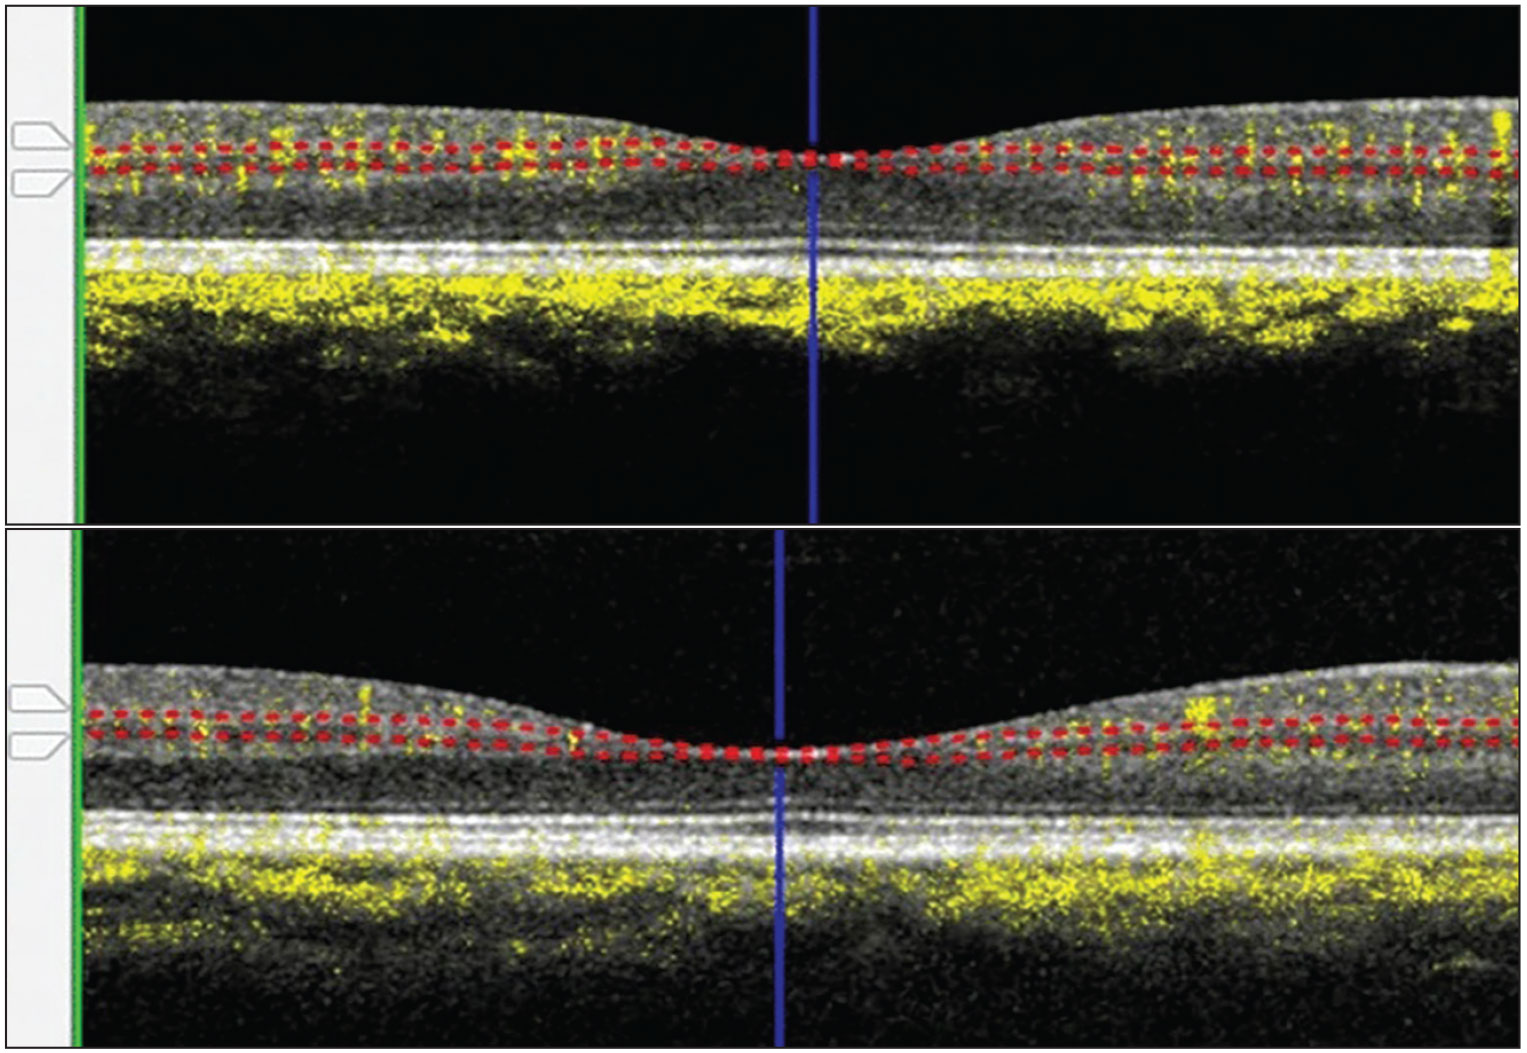

Representative optical coherence tomography images of the intermediate capillary plexus slab of a patient without COVID-19 (top) and one with severe COVID-19 demonstrate corresponding vessel densities of 33 and 18 percent, respectively. (Open access from Kalaw FGP, Warter A, Cavichini M, et al. Retinal tissue and microvasculature loss in COVID-19 infection. Sci Rep. 2023;13:5100. Published online March 29, 2023.) |

The study found that severe COVID-19 patients had significantly lower mean vessel density from the three inner retinal layers evaluated (24.20, least square mean) than mild COVID-19 patients (26.18, p=0.0057) and controls (26.28, p=0.004). Vessel density in mild COVID-19 patients didn’t differ significantly from normal participants (p=0.87). The analysis used pooled data from the three measured inner retinal layers.

- Significantly lower intermediate (Figure) and deep capillary plexuses (p<0.05).